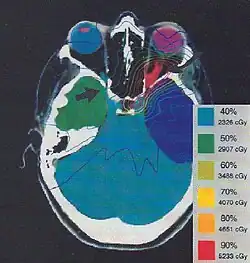

Treatment

Most ophthalmologists will not advocate any treatment unless visual loss is present and ongoing. Reports of patients with ONSM having no change in their vision for multiple years are not uncommon. If loss of vision occurs, radiation therapy will improve vision in about ⅓ of cases, and preserve vision in about ⅓ of cases. Surgery has traditionally been associated with rapid deteroriation of vision. However, newer surgical techniques may prove better for the treatment of ONSM.[4][6][7]